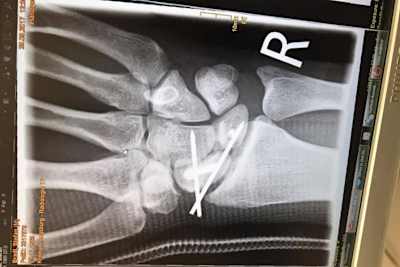

Bradl wurde in einem gut zweistündigen Eingriff von Dr. Stefan Krischak im Klinikum Augsburg die rechte Hand gerichtet. Das Mondbein und das Kahnbein waren um mehr als drei Millimeter auseinander gedriftet, das skapholunäre Band, welches die beiden Knochen verbindet, war beschädigt. "Ich bekam einen Draht eingesetzt mit einem Haken", erzählte Bradl SPEEDWEEK.com. "Der Haken ist am Mondbein befestigt, er wird dafür sorgen, dass das Band heilt und alles so zusammen kommt, wie es zusammen gehört. Leider ist der Heilungsverlauf sehr langwierig." Mitte November muss der Bayer erneut unters Messer, dann wird der Draht aus der Hand entfernt. Frühestens zwei Wochen nach der OP ist Bradl wieder einsatzfähig. Wie es 2018 weitergeht, weiß der Moto2-Weltmeister von 2011 nicht. "Wenn das mit Red Bull Honda nicht klappt, habe ich einen Plan B und C", versichert der 27-Jährige.